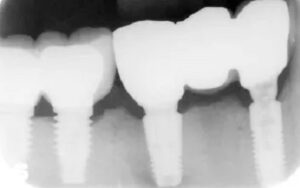

Protect your smile in Balwyn North from gum disease with our expert dental care. Visit us for comprehensive treatments and prevention strategies to maintain optimal oral health. Gum Disease Treatment in Balwyn North